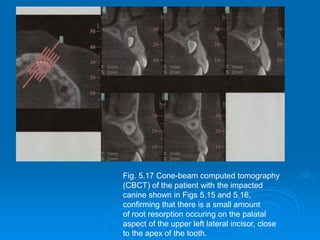

Fig. 5.17 Cone-beam computed tomography

(CBCT) of the patient with the impacted

canine shown in Figs 5.15 and 5.16,

confirming that there is a small amount

of root resorption occuring on the palatal

aspect of the upper left lateral incisor, close

to the apex of the tooth.